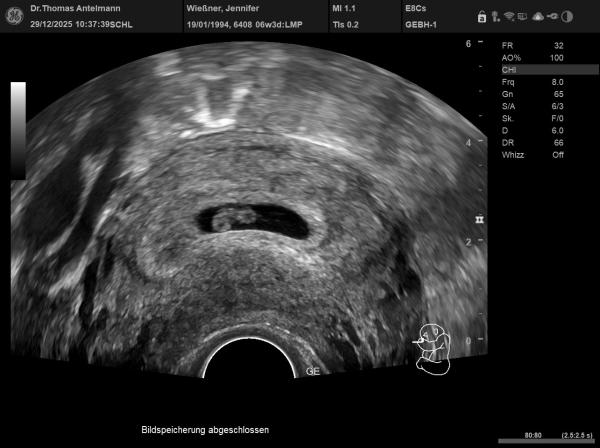

Hey ihr Lieben, Vielleicht sind ja Experten unter euch ;) Es ist unser 4. Baby und mich würde einfach interessieren, ob die Tendenz eher bei Team Rosa oder blau liegt. Viel Spaß ;)

Bild zu Ramzi-Methode Team blau oder rosa - Forum für August - Mamis

Noch ein weiteres bild